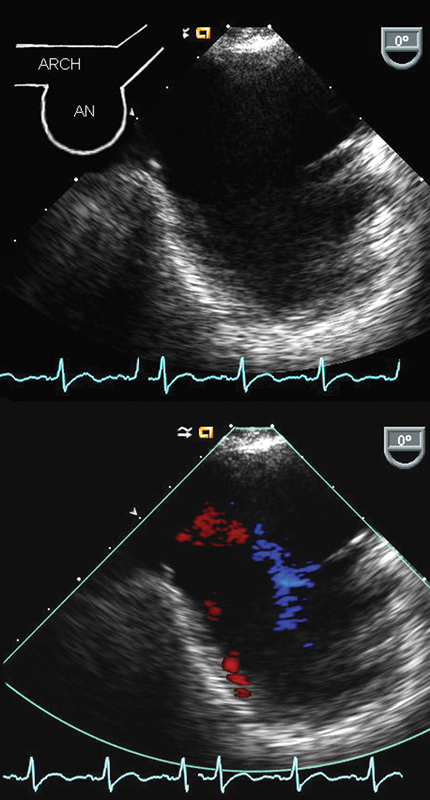

فحوصات تشخيصية لبعض امراض القلب والشرايين التاجية